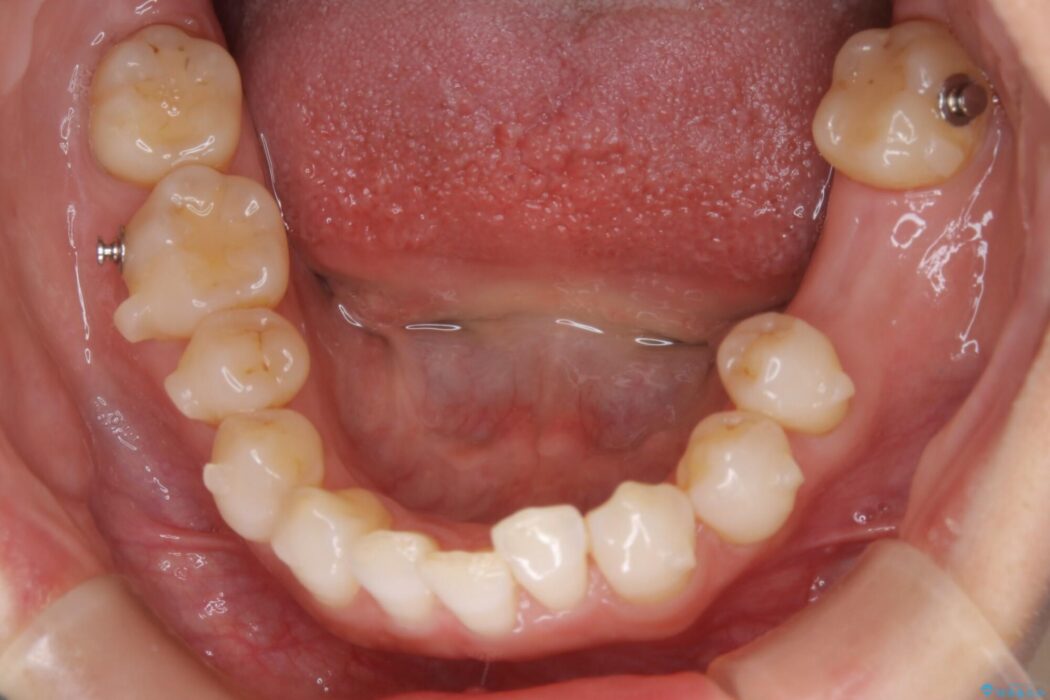

治療計画を立てる上で詳しく精密検査をしたところ、左下の6番目の歯につきまして治療が必要な状態であることが分かり、かぶせ物を外し、内部を確認しました。

結果としては深い部分で根が破折してしまっていました。

破折の処置としては基本的に抜歯が選ばれます。

悪くなっている歯の放置はできないと判断しましたので、患者様と様々な治療プランを相談した上で、最終的に該当の歯は抜歯をして噛み合わせを改善し、その後インビザラインでの矯正治療を行うこととしました。